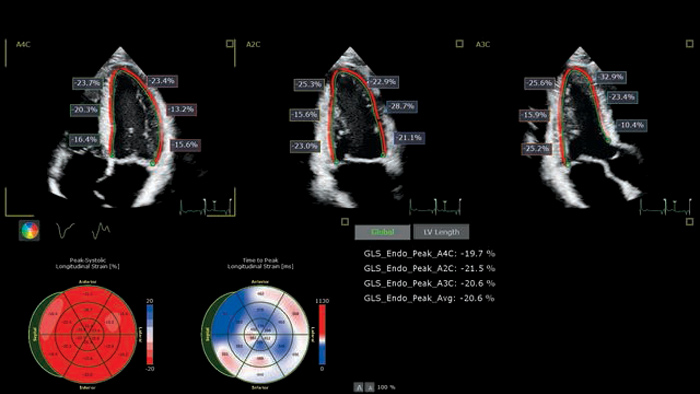

Las herramientas de deformación automatizadas pueden simplificar la evaluación de la función ventricular derecha, con el consiguiente impacto en los protocolos asistenciales de los pacientes con COVID-19.

Uso de herramientas ecográficas avanzadas para evaluar la disfunción cardiaca asociada a tratamientos oncológicos

Los métodos que consumen mucho tiempo se ven superados por el sistema de ultrasonidos con inteligencia anatómica (AIUS) de Philips en lo que respecta a la prevención de la cardiotoxicidad.